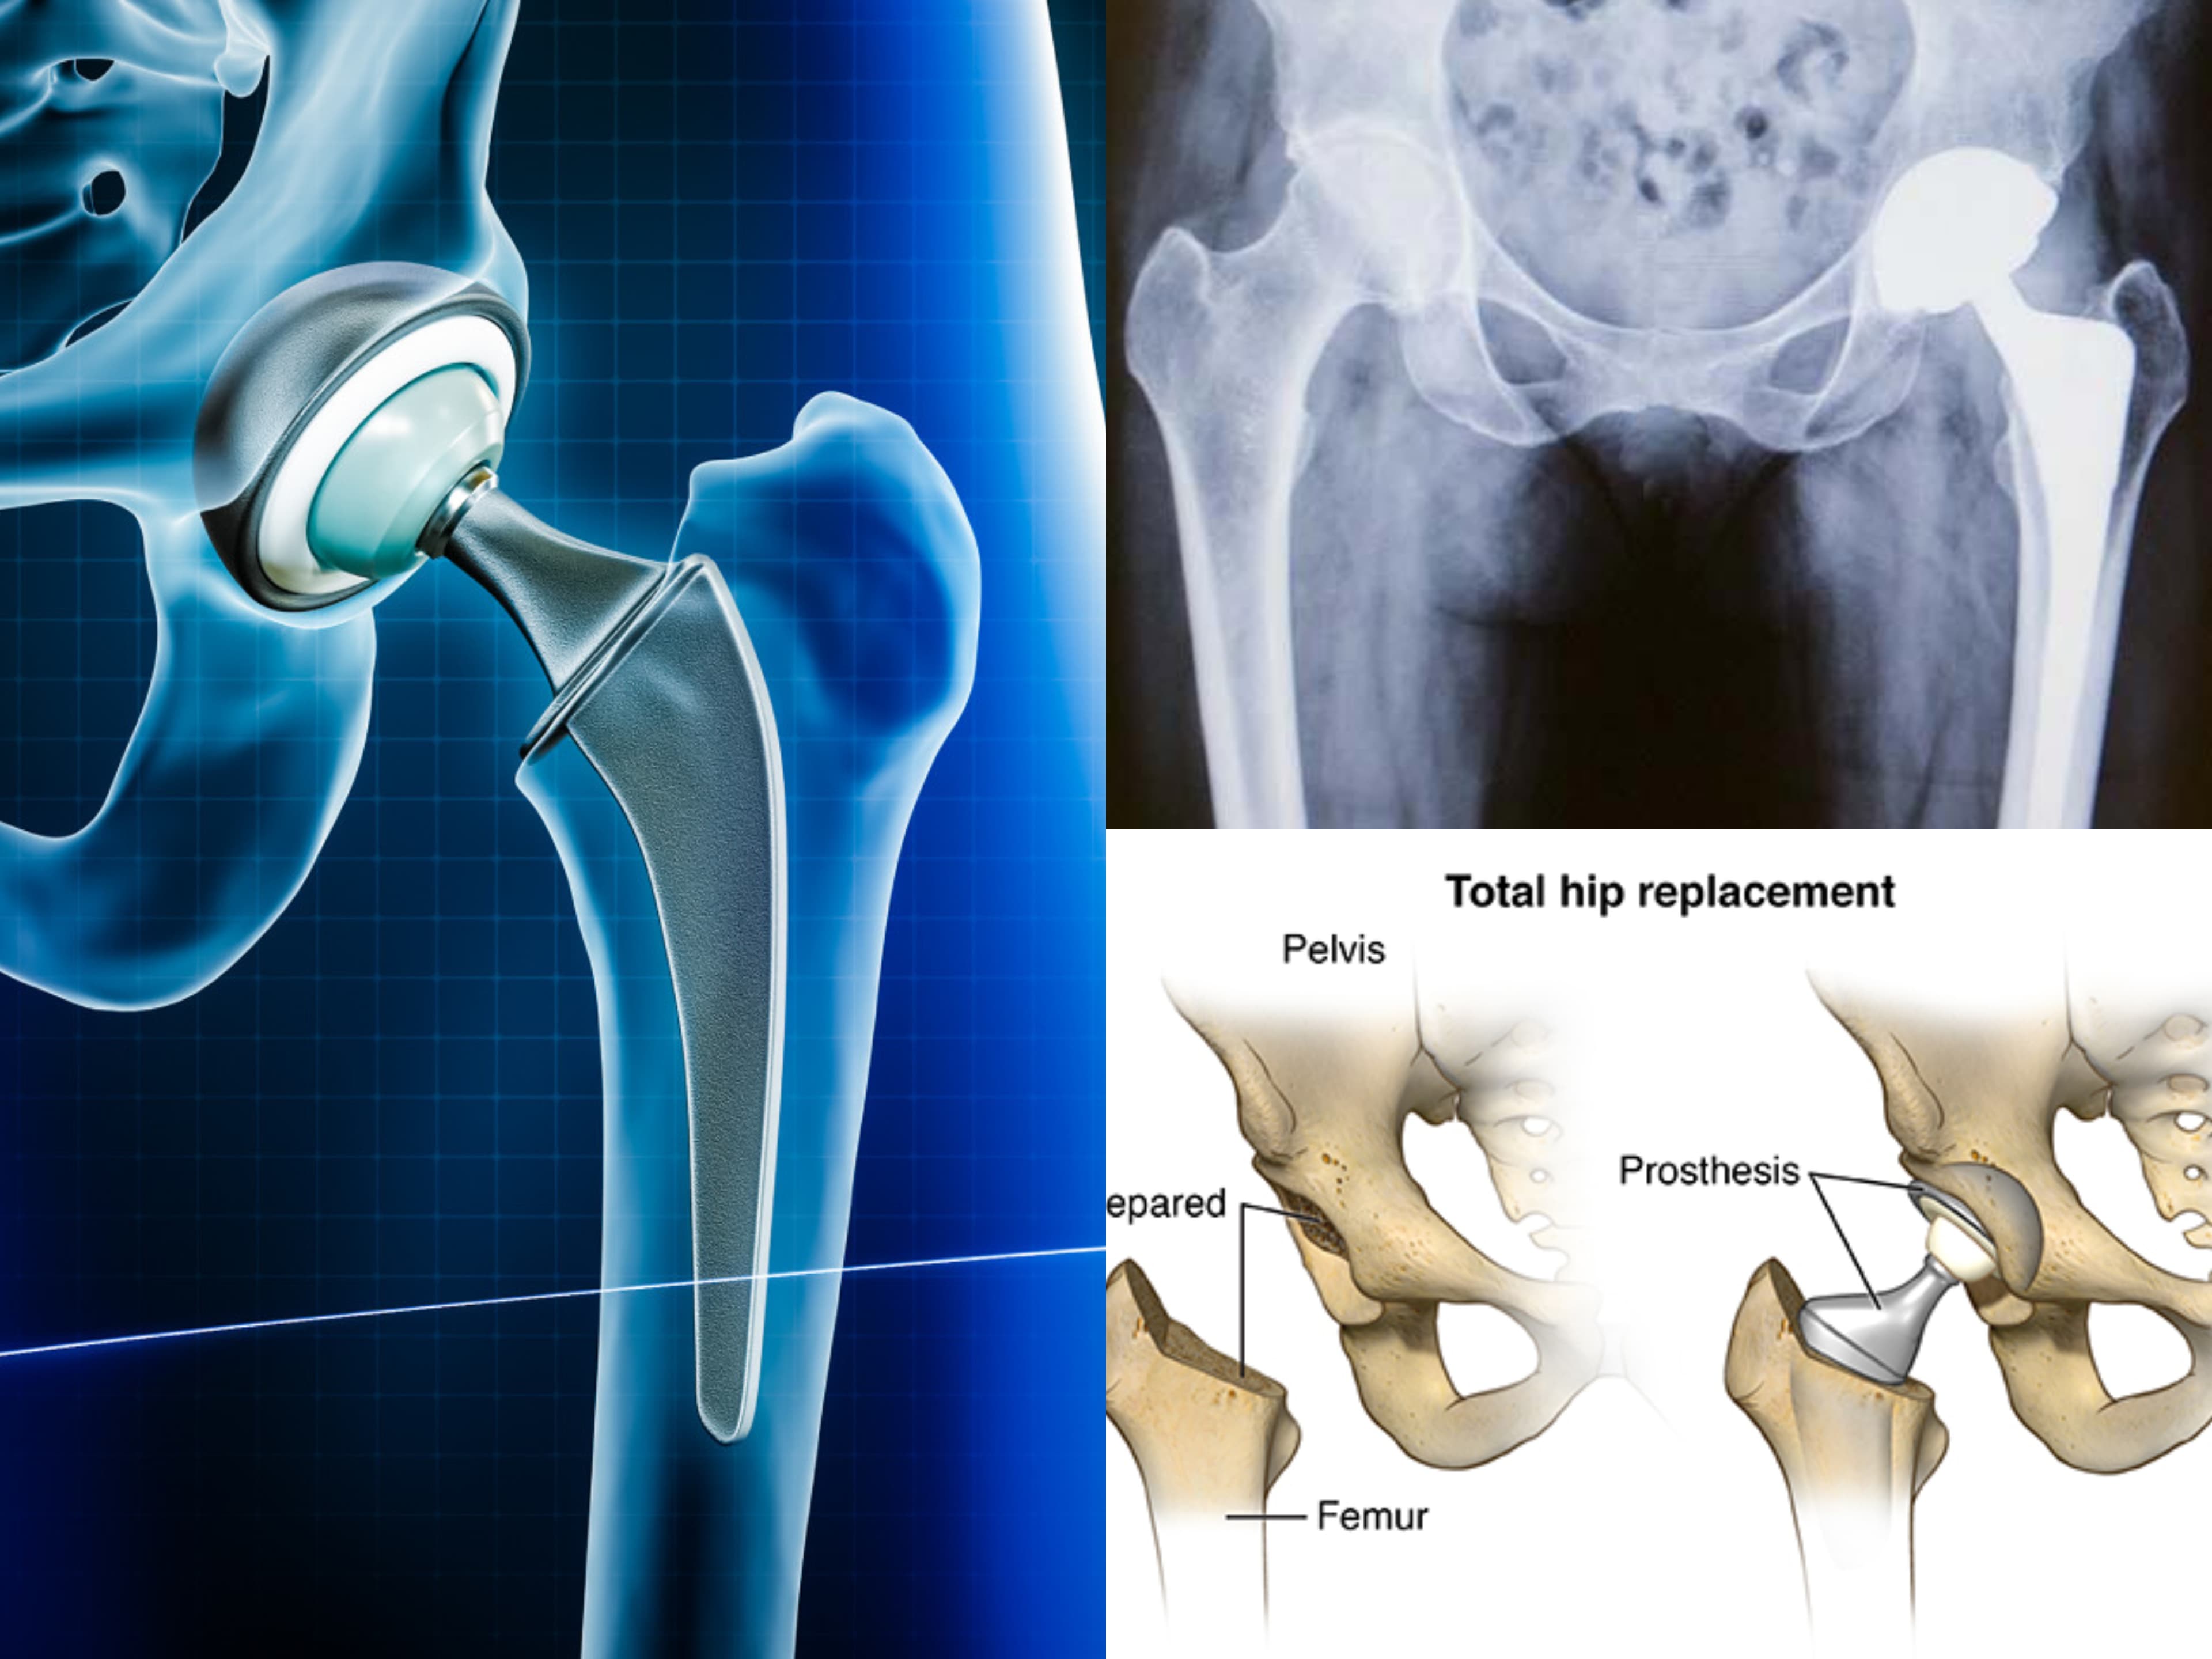

Many users have shared their positive experiences of successful surgeries, such as ACL keyhole surgery, hip replacement, and knee replacement surgeries. The staff is helpful and courteous in assisting patients with formalities and appointments.

- Dr. Vivek Patil is one of the best orthopedists in Hubli for major surgeries.